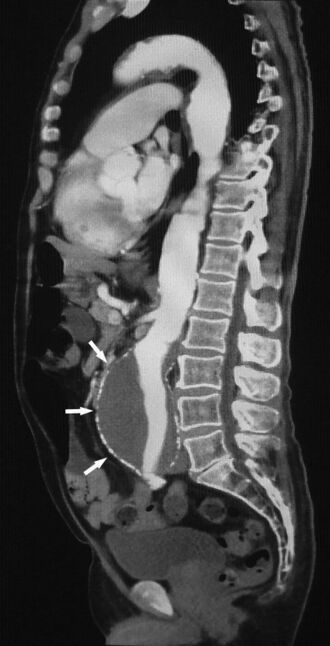

SagitalAAA.jpg

Sagittal thin slice of a computed tomography angiography abdominal aortic aneurysm (AAA) (arrows)

Aorta and great arteries

CTA can be used in the chest and abdomen to identify aneurysms in the aorta or other major blood vessels. These areas of weakened blood vessel walls that bulge out can life-threatening if they rupture. CTA is the test of choice when assessing aneurysm before and after endovascular stenting due to the ability to detect calcium within the wall.[3] Another positive of CTA in abdominal aortic aneurysm assessment is that it allows for better estimation of blood vessel dilation and can better detect blood clots compared to standard angiography.[4]